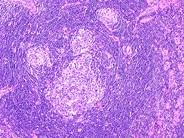

Castleman lymphadenopathy - 1.

Low-magnification view of lymph node in a patient with Castleman lymphadenopathy. Multiple lymphocyte depleted germinal centers of variable size are present. The mantle zone has the characteristic "onion skin" swirling pattern. Marked increase in interfollicular blood vessels is also seen.